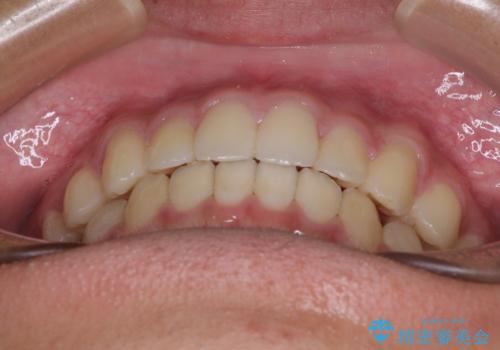

突き上げによる隙間を予防する為に、深い咬み合わせを改善するような治療計画としました。咬み合わせを改善させることはできましたが、隙間は後戻りしやすいので、通常の下顎前歯のみではなく、上顎前歯2本もワイヤーで保定を行いました。

高校生ということで、非常に短期間で治療を終えることができました。